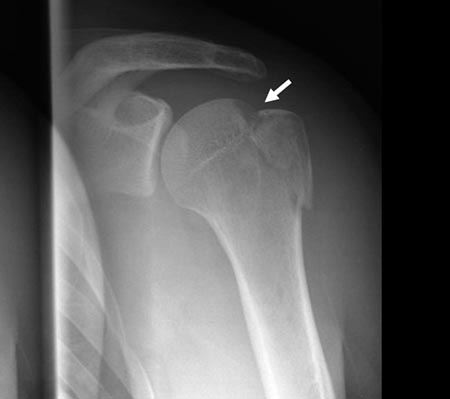

Figura 1A: Fractura con desplazamiento del troquiter mayor a 5 mm./ Figura 1B: Misma fractura en TAC 3D. Conminuta a 3 fragmentos y desplazada. Flechas: fragmentos óseos.

Si la reducción de los fragmentos es correcta en las imágenes por radioscopía, la fijación temporal de los fragmentos óseos con clavijas percutáneas es llevada a cabo. Posteriormente y según el tamaño de los fragmentos se utilizan tornillos canulados de 2.7 mm, 3,5 mm y/o 4.5 mm. Es importante remarcar nuevamente la no resección de los tejidos blandos (manguito rotador) de los fragmentos óseos. En 4casos de fracturas conminutas la reducción y osteosíntesis de los fragmentos fue lograda a través de los tejidos blandos y no del propio tejido óseo. Si la reducción de los fragmentos no es correcta la inspección del lecho de la fractura, primero a nivel articular y luego a nivel subacromial, es llevada a cabo con el fin de facilitar la misma mediante la remoción de tejidos interpuestos. En todos nuestros pacientes fueron colocados no menos de 3 tornillos de fijación (Fig. 1 y 2).